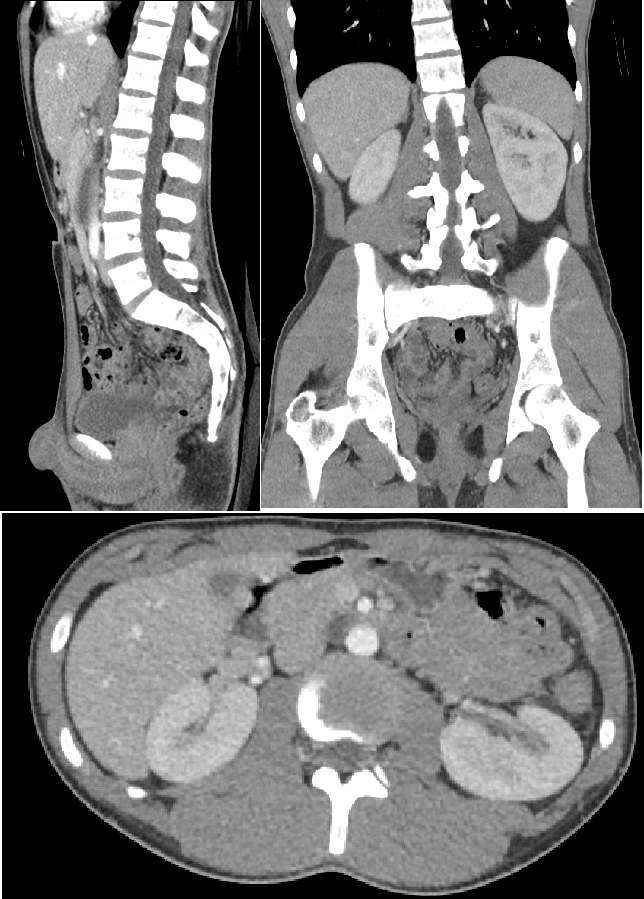

CT는, 엑스레이 사진을 여러 장 찍어 우리 몸의 단면을 컴퓨터로 재구성하는 촬영 방법입니다. 그래서, '컴퓨터로 계산하여(computerized) 단면(tomo)을 기록했다(graphy)'란 뜻으로 computerized tomography(컴퓨터 단층촬영), 줄여서 C.T.라고 부릅니다. tomo는 잘랐단 뜻이에요. ana-tomy는 신체를 자르는 해부란 뜻입니다. 촬영하는 단면은 주로 3가지로 나뉘는데요, 각각 아래 복부와 골반의 CT에 잘 나타나 있습니다. 첫 번째 왼쪽 사진은 시상 단면(sagittal section)이고, 둘째는 관상 단면(coronal section), 마지막으로 아래 단면은 횡단면(transverse section)이라고 합니다. 해부학적 단면에 관한 용어는 아래 7화 포스트에 자세히 설명되어 있습니다.

Computed tomography of the abdomen and pelvis, Mikael Häggström, M.D.